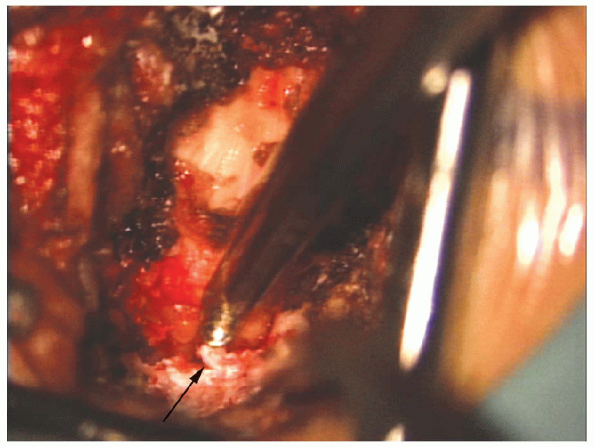

FIGURE 17-18. Bone wax (arrow) on a small elevator can be used to control bleeding from cancellous bone.

|